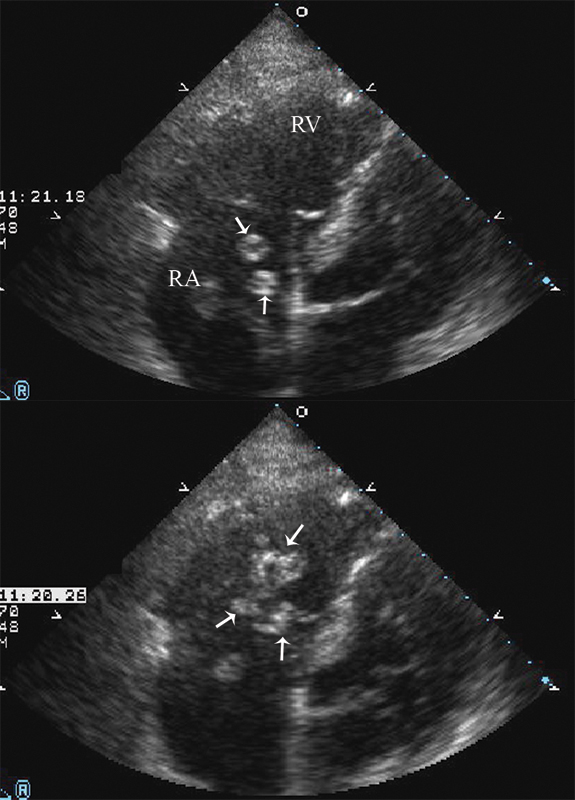

فحوصات تشخيصية لبعض امراض القلب والشرايين التاجية